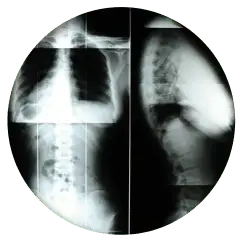

X-RAYS